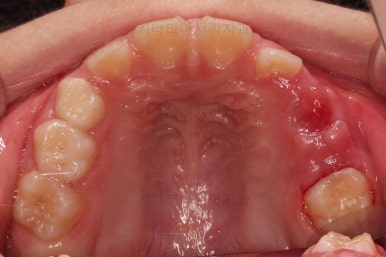

초진 시 입안의 모습입니다.

아래쪽 치열이 전반적으로 윗니보다 앞쪽에 위치한 전형적인 앵글씨 3급 부정교합인데요.

어금니에서부터 앞니까지 아랫니가 윗니보다 앞쪽에 위치하네요.

특히 앞니는 아랫니가 윗니보다 나와있는 "반대교합" 상태였고요.

또한 위아래로 겹침이 없고 떠있는 "개방교합" 상태였어요.

즉, 앵글씨 3급 부정교합 - 반대교합 - 개방교합 등 굉장히 복합적인 교합의 문제를 가진 환자였습니다.

왼쪽 하단 사진의 어금니에 있는 금속성 장치는 band & loop(밴드 앤 루프)라고 하는 공간유지장치인데요. 오래 써야하는 유치가 일찍 빠지는 바람에 그 공간을 잡아두는 장치입니다.